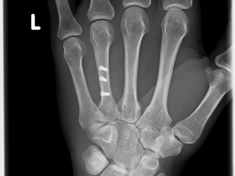

Röntgenbilder